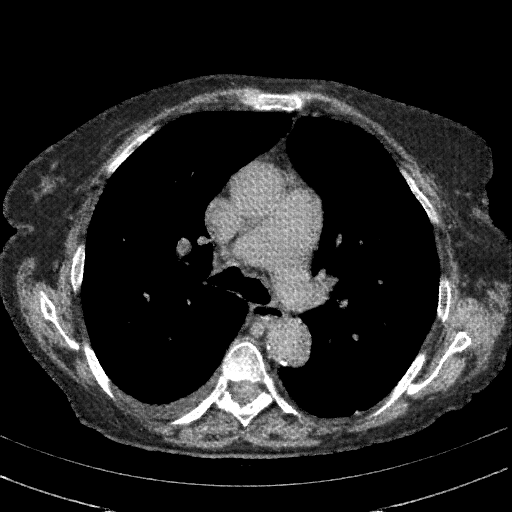

Original VENOUS CT scan

Full window (WL 1023.5, WW 4095 β†’ Low βˆ’1024, High +3071)

Lung window (WL -600, WW 1500 β†’ Low βˆ’1350, High +150)